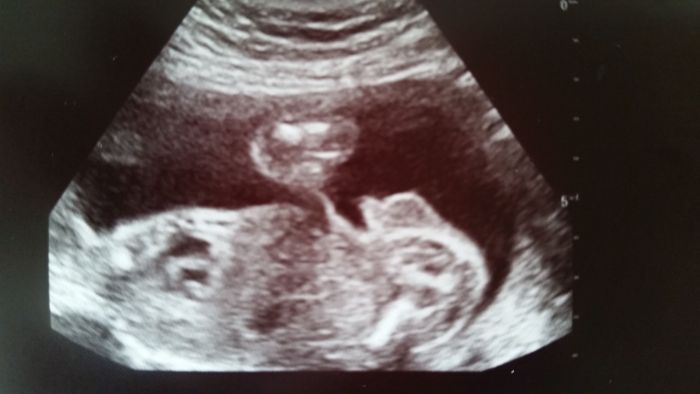

...ještě foto...toho našeho pindíka :-)

...tak  snad už...